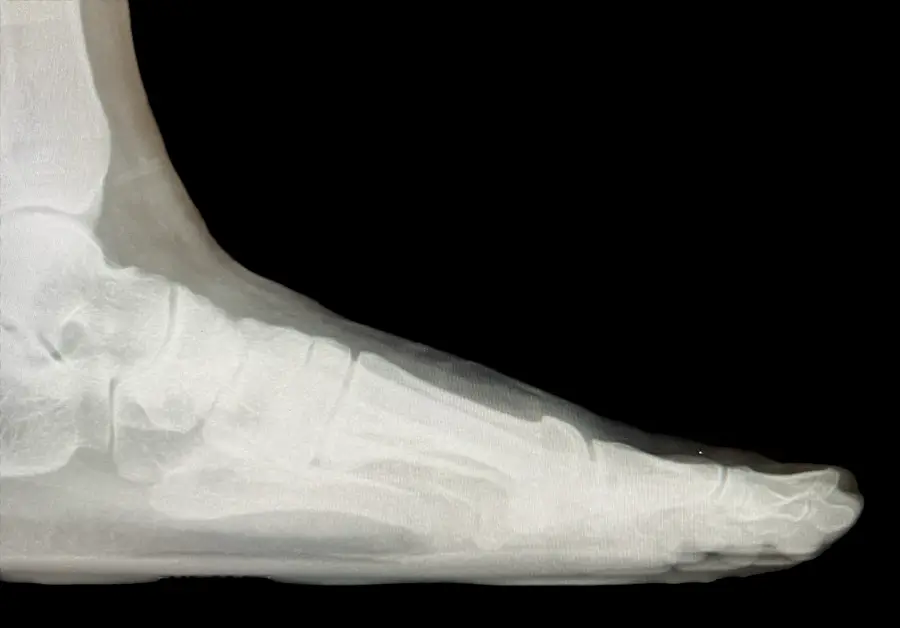

Surgical Intervention at Stepwell Institute is never a “one-size-fits-all” solution. We view surgery as a precise tool used to restore the natural biomechanics of the foot and ankle when non-invasive methods have reached their limit. Our philosophy centers on individualized surgical planning—using advanced imaging to map out the procedure before you ever enter the operating room. From correcting bunions and hammertoes to performing ligament repairs and fracture fixations, Dr. Yakov utilizes techniques designed to minimize trauma to the surrounding tissues, thereby reducing the risk of complications and ensuring a more stable, long-term result for our patients.

Stepwell Institute distinguishes itself by offering NJ patients access to the most advanced surgical modalities in modern podiatry. We specialize in Surgical Intervention, which utilize smaller incisions and specialized instruments to reduce post-operative pain and scarring. For more complex cases, we employ 3D-printed surgical guides and biological grafts to enhance the body’s natural healing ability. By choosing Stepwell Institute, you benefit from a specialized recovery plan where Dr. Yakov and our team prioritize early, safe mobilization. Our goal is to provide a definitive surgical solution that allows you to return to the active New Jersey lifestyle you love with confidence and strength. confidence and strength.

Our Case Study